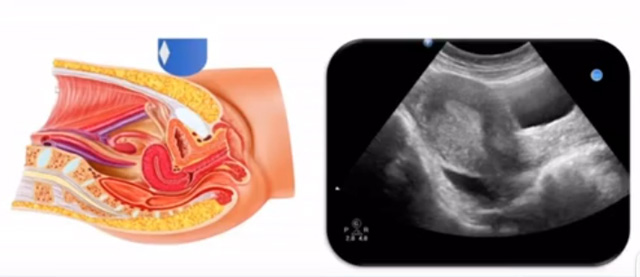

女性生殖系統(tǒng)包括內(nèi)、外生殖器官及其相關(guān)組織以及鄰近器官,其中內(nèi)生殖器是我們超聲檢查的主要對(duì)象。那么內(nèi)生殖器包括陰道、子宮還有輸卵管及卵巢。輸卵管及卵巢稱為子宮附件。子宮是倒置梨形,但是它是空腔厚壁肌性器官。它的正常值在育齡婦女。超聲探頭放在貼近腹壁盆腔上面位置,來看這個(gè)子宮在超聲上面的表現(xiàn)。從輪廓上來講,和示意圖是一樣的。這就是在超聲上面顯示的一個(gè)子宮的圖片。子宮在不同的時(shí)期與子宮頸的比例。成年婦女指的是育齡婦女為2:1子宮體是比較大的,嬰兒期為1:2說明宮頸比較大,絕經(jīng)期1:1。所以我們?cè)诳吹阶訉m圖時(shí)候可以根據(jù)宮體宮頸比例大致可以推測(cè)屬于哪個(gè)時(shí)期的婦女。另外還可以根據(jù)比例大小來推斷是一個(gè)正常子宮還是異常子宮。

子宮從外到內(nèi),漿膜層、肌層、粘膜層。宮體部宮頸為梭形結(jié)構(gòu)。宮腔為上寬下窄的三角形,連接為峽部。子宮有什么功能呢?月經(jīng)血產(chǎn)生跟排出通道,精子運(yùn)行通道受精作用。囊胚著床及胎兒發(fā)育、生長(zhǎng)的場(chǎng)所。分娩時(shí)產(chǎn)生宮縮使胎兒、胎盤娩出。未孕的子宮是很小的,已孕子宮就非常大,平均胎兒都有6斤重。所以這個(gè)后壁就體現(xiàn)出來。輸卵管由子宮角部向外延伸,為一對(duì)細(xì)長(zhǎng)而彎曲的管道,呈管狀中空結(jié)構(gòu),大概長(zhǎng)度是8-14厘米,粗1-4毫米,它的下方為卵巢和闊韌帶。間質(zhì)部是厚一點(diǎn)的,峽部是比較窄的地方,壺腹部,漏斗部。正常情況下,輸卵管在普通超聲DR難以顯示。